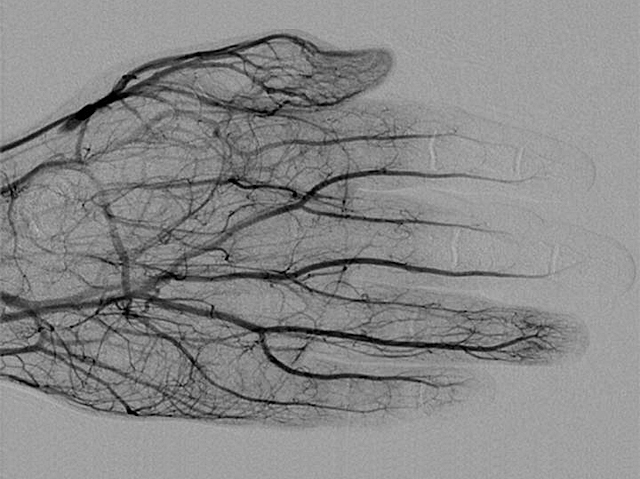

Cold Snap

In search of the best way to treat frostbite saving digits and limbs

Doctors often compare notes, sharing their experiences and 'best practice' on how to treat diseases. When cases are rare, or spread over the globe, published medical reviews help to bring international findings together, looking for patterns in the pooled information that might lead to better treatments. A recent review on frostbite suggests injection with tissue plasminogen activator, a protein involving in reducing blood clots, has saved many digits from amputation, including the top two fingers of this 54-year old man. Clotting is one by-product of the body’s response to ice crystals formed inside blood vessels (seen here in black) – so it’s no surprise that heparin, a drug that helps 'thin' the blood, also helped in his treatment. Combination treatments like these may help doctors prepare for the ongoing rise in cold injury cases.